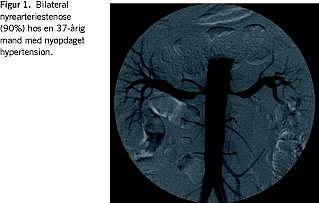

To måneder efter første indlæggelse blev der foretaget NVK med selektiv reninopsamling og aortografi i samme seance. Selektiv opsamling af elektrolytter fra nyrevenerne viste ingen sideforskel. Noget overraskende viste reninbestemmelsen øget reninaktivitet fra venstre nyre. Da der rejstes tvivl om, hvorvidt der evt. kunne være sket en ombytning af glassene, blev undersøgelsen (NVK) gentaget halvanden måned senere med samme resultat. Aortografien, der blev udført samtidig med den første NVK, viste udtalt bilateral nyrearteriestenose, men ingen sikre tegn på arteriosklerose (Figur 1 ). Ved den efterfølgende ballonudvidelse med stentanlæggelse blev dog vurderet, at stenoserne var på arteriosklerotisk basis.